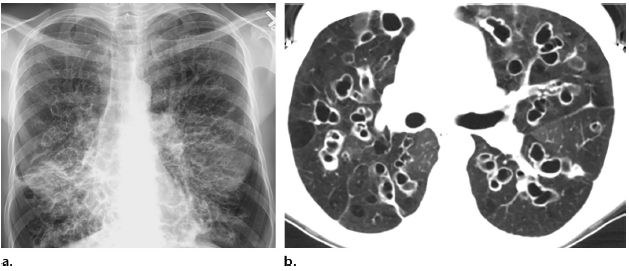

支氣管擴(kuò)張的診斷主要依據(jù)患者的病史、癥狀和體征,以及輔助檢查如高分辨率CT掃描等,醫(yī)生會根據(jù)患者的具體情況進(jìn)行綜合分析,以確定診斷。